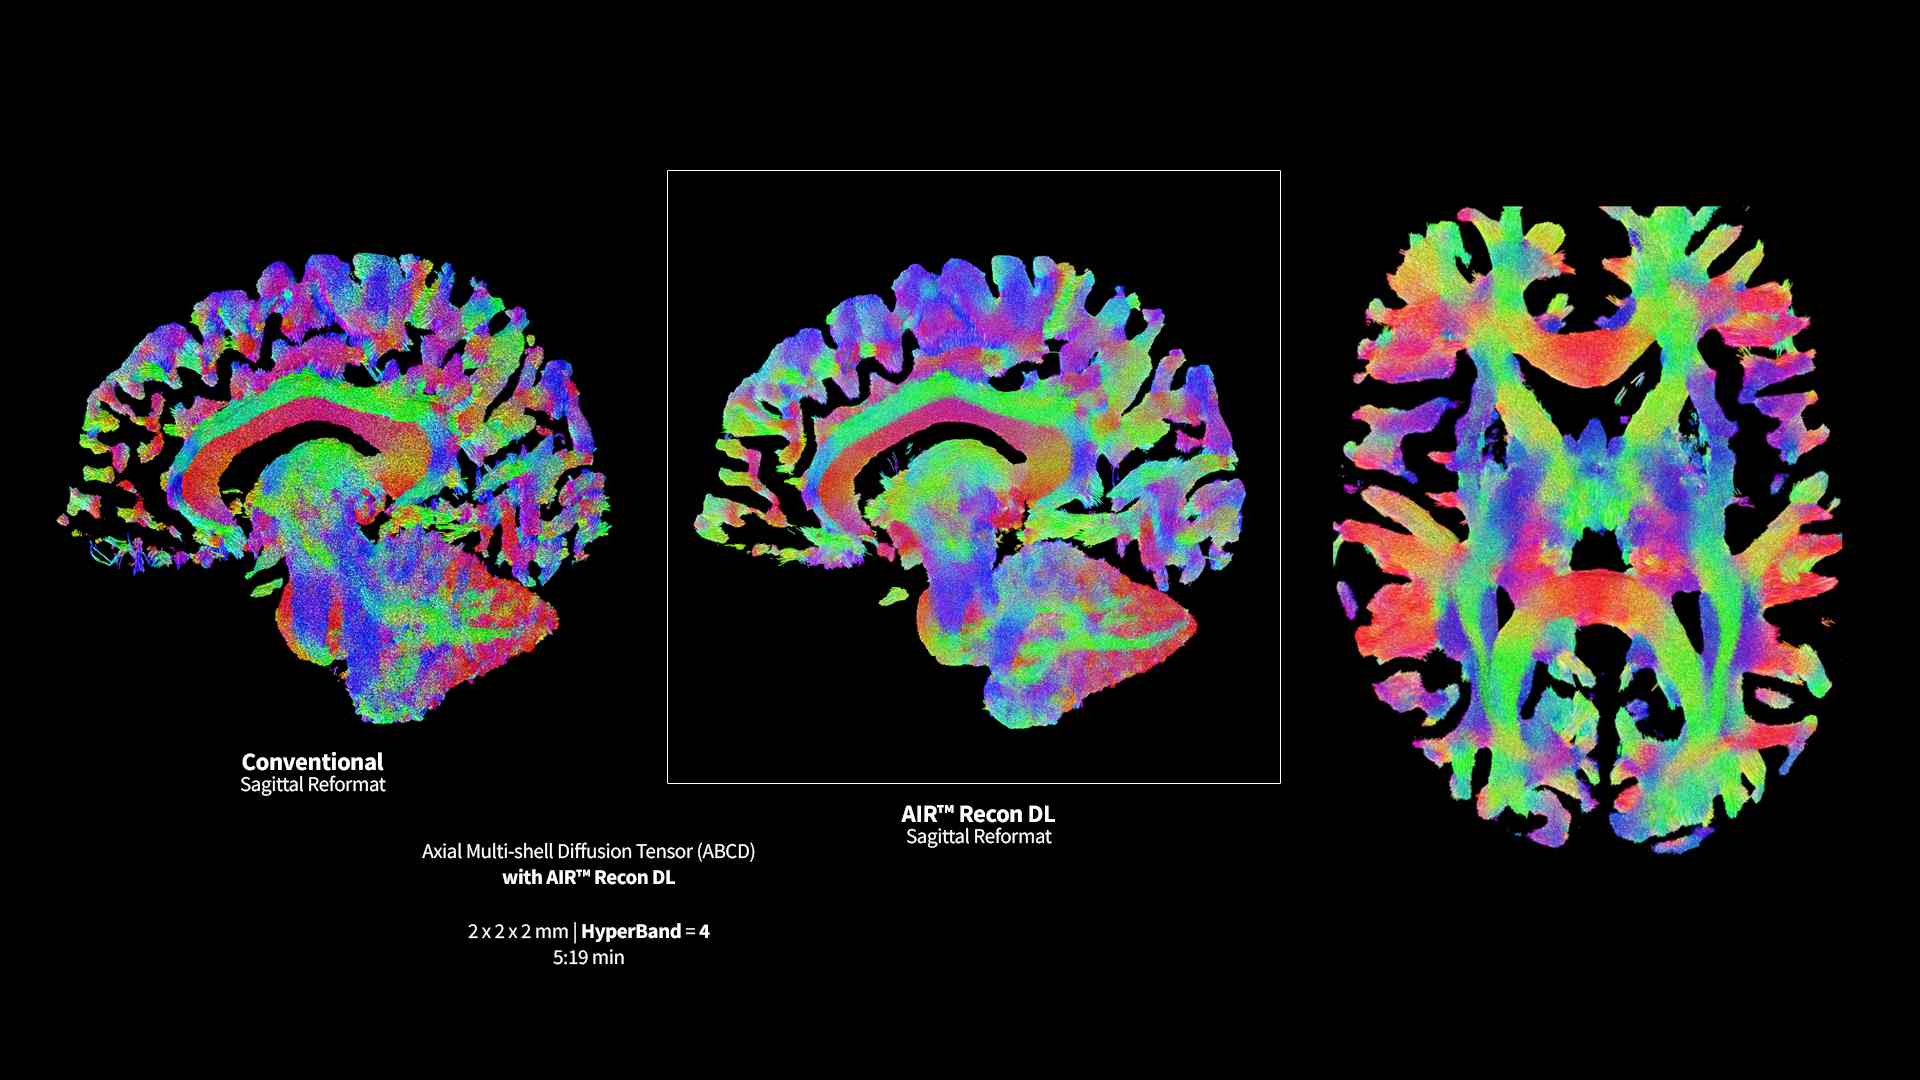

Revolutionary, deep-learning-based reconstruction techniques such as AIR™ Recon DL provide sharper, clearer, and accurate images

Pin-sharp image quality and exceptional speed with AIR Recon DL and Sonic DL​

Experience pin-sharp precision and remarkable speed with a 3T SIGNA Premier MRI scanner, coupled with AIR Recon DL and Sonic DL™.

SIGNA Premier exemplifies many powerful robust attributes that makes it an exceptional MR for academic institutions. Alongside the SuperG gradients, which are proficient in executing the Human Connectome Protocol (HCP), the system has impeccable fMRI stability, a high RF-channel count with AIR Coils and a suite of deep learning applications.